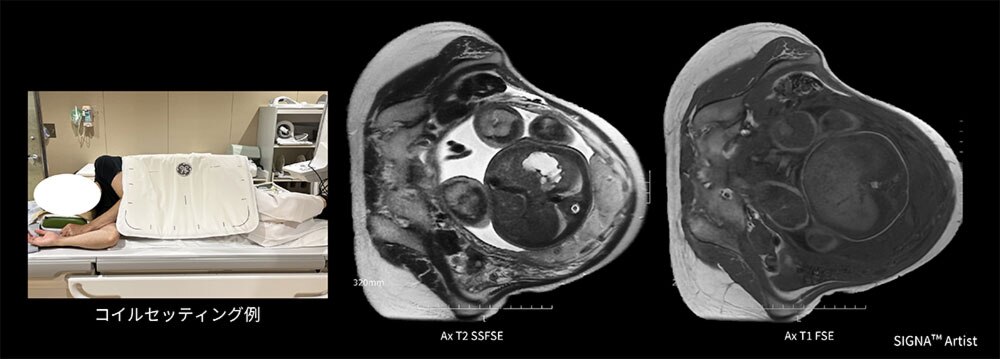

Case2 妊婦の子宮胎盤検査

30代の妊婦。重複子宮の疑いにて経腟分娩可能か評価する目的にてMRI検査を実施。

検査時35週で推定胎児体重が2384gであり、本人より仰臥位困難の訴えがあったため、側臥位でAIR™ Coilの向きを変えて腹部全体にコイルを覆いポジショニングを行った。側臥位にすることで患者さんの負担も少なくセッティングもスムーズで検査が施行でき、出産方法の決定に貢献できた一例(図4)。

図4 妊婦の子宮胎盤検査におけるAIR™ Coilのセッティング例と臨床画像